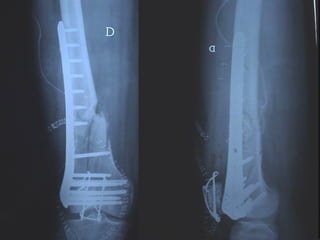

Dal Gennaio 2000 al Febbraio 2006 abbiamo trattato 167 fratture chiuse  con placca percutanea  in 164 pazienti :  27 lesioni diafisarie di gamba, 12 piloni tibiali ,  11 fratture prossimali di tibia, 36 fratture sovracondiloidee di femore, 17 fratture diafisarie di femore, 43 fratture metaepifisarie prossimali di omero, 21 diafisarie d’omero.  156 guarigioni 8 fallimenti

Dal Giugno 2002 al Dicembre 2004 abbiamo trattato 5 fratture esposte: 3 di tibia e 2 di ulna 5 guarigioni

I buoni risultati ottenuti dipendono da 5 punti fondamentali:   una accurata riduzione percutanea della frattura  precise vie di accesso  l’utilizzo della placca che consenta il più lungo braccio di leva possibile il pretensionamento della placca  una sintesi con un ridotto numero di viti

Dal Gennaio 2000 al Dicembre 2005 27 placche LISS di femore